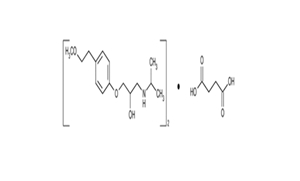

Naproxen Tablets USP

| 250 mg | Tablet | Rx | Naprosyn |  | 62207-745-43 62207-745-47 62207-745-49 |

Medication Guide |

| 375 mg | Tablet | Rx | Naprosyn |  | 62207-746-43 62207-746-47 62207-746-49 |

Medication Guide |

| 500 mg | Tablet | Rx | Naprosyn |  | 62207-747-43 62207-747-47 62207-747-49 |

Medication Guide |